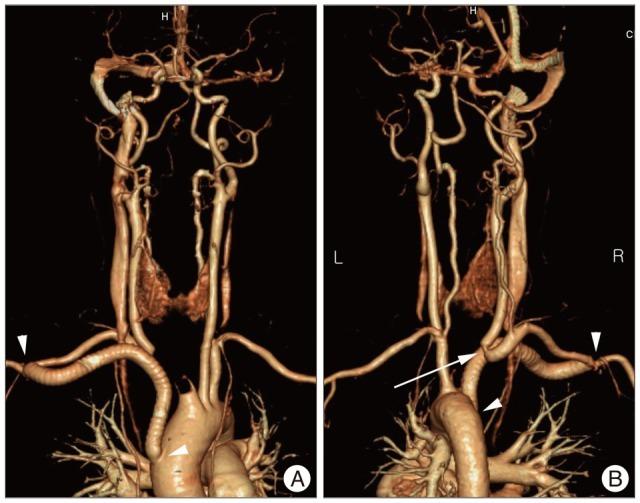

Tracheoinnominate artery fistula is a critical complication of tracheostomy. The most important factors influencing patient outcome are prompt diagnosis, immediate control of bleeding with a patent airway, and emergency operation with or without interruption of the innominate artery. Here, we report a case of tracheoinnominate artery fistula in a 40-year-old woman with cerebrovascular accident who was successfully managed with an aorta-axillary artery bypass.

气管无名动脉瘘是气管切开术的一种严重并发症。影响患者预后的最重要因素是及时诊断、在气道通畅的情况下立即控制出血以及对无名动脉进行或不进行阻断的急诊手术。在此,我们报告一例40岁脑血管意外女性患者发生气管无名动脉瘘的病例,该患者通过主动脉-腋动脉旁路移植术成功得到治疗。